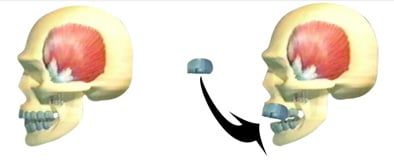

The Temporomandibular Joint (TMJ) connects the lower jaw to the temporal bone on the side of the head. You can feel it by placing your fingers just in front of your ears while opening and closing your mouth. These flexible joints allow smooth movement for chewing, speaking, and yawning. When the TMJ isn’t functioning correctly, it can lead to TMD—a cycle of pain, muscle spasms, and jaw problems that can severely impact your daily life. At Tomlinson Dental, our Tampa team offers personalized treatment plans to correct TMJ dysfunction and relieve symptoms. TMD encompasses a range of conditions stemming from an unbalanced or uncomfortable TMJ, often presenting as pain in the jaw, muscles, and surrounding areas. When teeth are missing, misaligned, or crowded, chewing and biting become unbalanced, causing the TMJ and associated muscles to work harder, leading to painful symptoms. Tomlinson Dental in Tampa provides comprehensive assessments and treatments for TMD, helping patients regain comfort and functionality. TMD can be categorized into three main types:

- Internal Derangement of the Joint – This refers to issues such as a displaced disc or injury to the condyle (the rounded part at the end of the jaw bone).

Phase I :

Generally speaking, it includes the fabrication of an orthotic. An orthotic is an acrylic device that is worn on the lower teeth 24 hours a day. The orthotic is designed to reposition the jaw to the correct neuromuscular position.

First we analyze the bite, decide which muscles are causing the pain, and where the current position of the bone is and the disc. All this is done with the aid of advanced equipment like the TENS unit, K7 jaw tracking, Sonography, EMG's and advanced x-rays like Tomography, CT Scans and MRI's of the TMJ.

This will help us determine the best and most comfortable position of the TMJ and the muscles. Once that position is determined, we place the orthotic on the lower teeth to keep the TMJ in that position.

Orthotics usually are worn for 4-6 months or until most of the symptoms are relieved. Once an orthotic is in use, the symptoms start gradually disappearing until we reach a point that both the doctor and the patient are satisfied with. This concludes Phase I of the treatment.

Bite Splints

Bite splints (plates) are effective in relieving TMD symptoms.

A bite splint provides an acrylic platform to bite against. Some bite plates move the mandible to a new position.

Generally, splints are worn part-time and for most people night time seems to be the best time to wear them.

NTI-TSS System

The NTI-TSS System is a type of mouth guard that is placed on the patient's upper teeth. This lets the lower jaw rest in its proper place and causes the teeth to subside from being able to clench together.

If you experience chronic headaches, please ask your doctor because the NTI-TSS System could work for you.